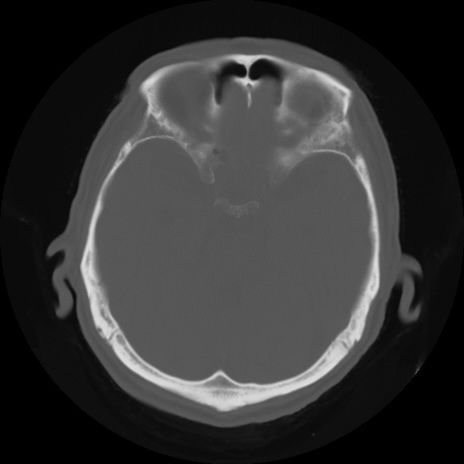

【頭部】症例5 CT(横断像)

症例5の画像所見と診断は?